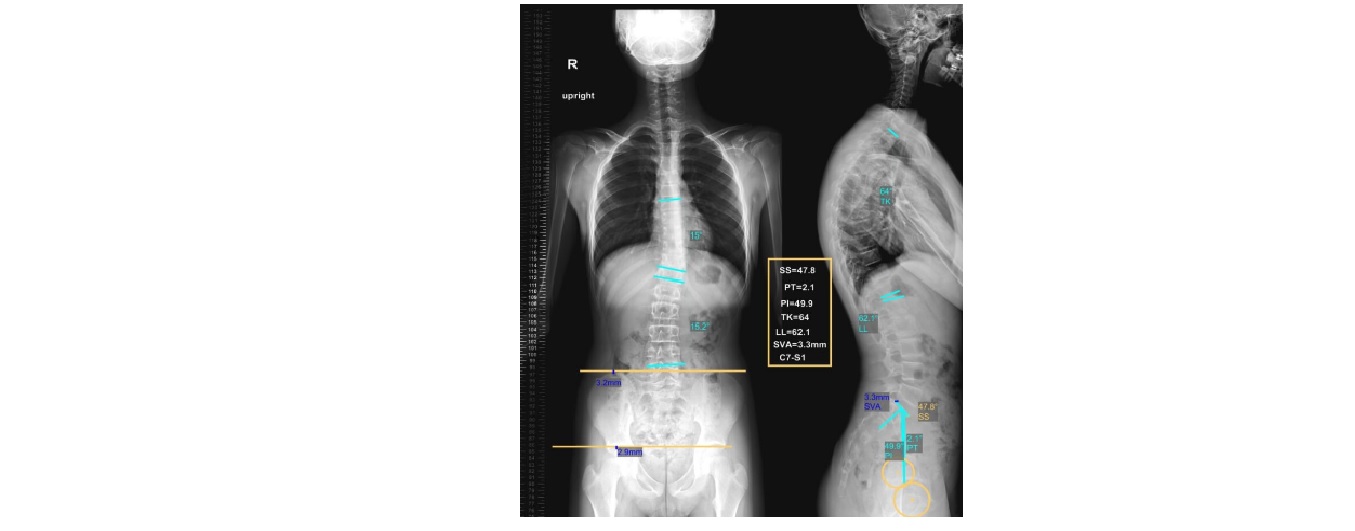

رادیوگرافی انحراف ستون فقرات

با دستگاه جدید و روز دنیا 2024 و کاملا اتوماتیک جهت تعیین میزان انحراف ستون فقرات:

رادیوگرافی کجی ستون فقرات گردنی یا سرویکال ، پشتی یا توراسیک ، کمری یا لومبار ، ساکرال لگنی کوکسیکس یا دنبالچه: جهت تعیین موارد فوق نیازی به ناشتایی یا آمادگی خاصی نمی باشد .بیمار در حالت ایستاده در نمای رخ و نیمرخ قرار گرفته و در طول انجام رادیوگرافی انحراف ستون فقرات باید تکان نخورده و جابجا نشود.https://kouroshradiology.ir

همکاری بیمار تا اتمام رادیوگرافی لازم بوده و هر گونه جابجایی باعث تغییر در زوایای محاسبه شده میگردد و نیاز به تکرار گرافی دارد.https://kouroshradiology.ir

لازم به ذکر است که تعداد مهره های گردن 7 عدد و تعداد مهره های پشتی 12 عدد و تعداد مهره های کمری 5 عدد می باشند.

گرافی های تهیه شده در داخل نرم افرار خاص آنالیز شده و میزان زاویه انحراف هر قسمت شامل :گردن یا سرویکال Cervical ، پشتی یا توراسیک Thoracic ، کمری یا لومبار Lumbar ، ساکروم و دنیالچه sacrococcygeal به صورت مجزا تعیین می گردد.https://kouroshradiology.ir